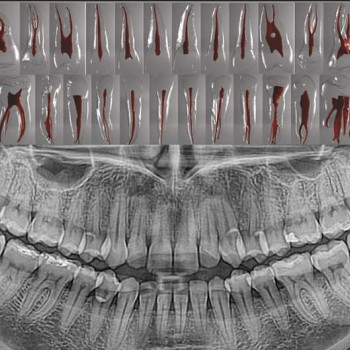

Пломбирование каналов зуба в Житомире - Страница 2